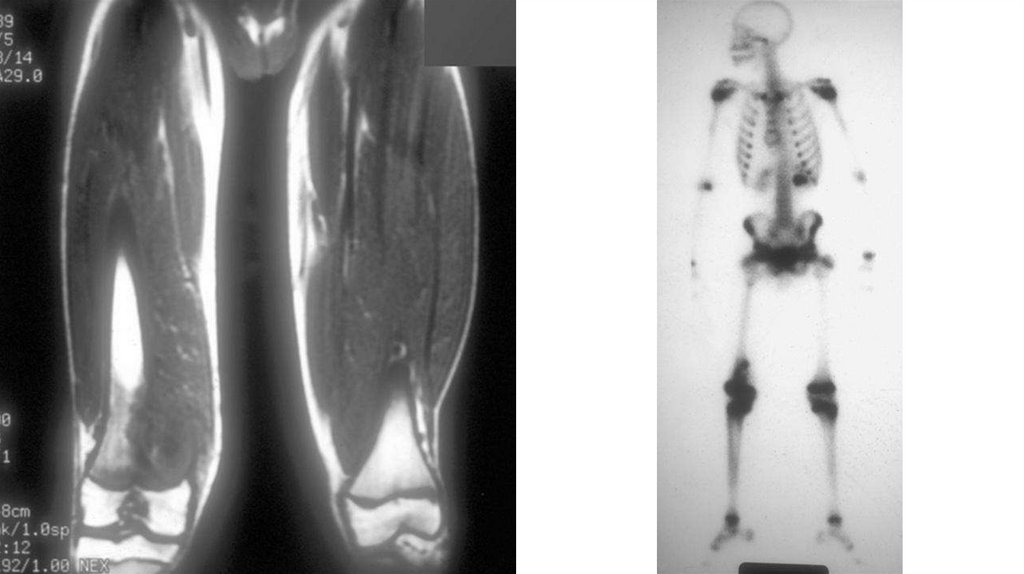

Диагностика

• Рентгенография (очаг деструкции, игольчатый периостит,

«козырек» Кодмана)

• КТ

• МРТ с контрастированием

• Сцинтиграфия с технецием

• Биопсия (высокий полиморфизм с наличием большого количества

митозов, наличие новообразованных остеоидных структур)

• Поиск метастазов